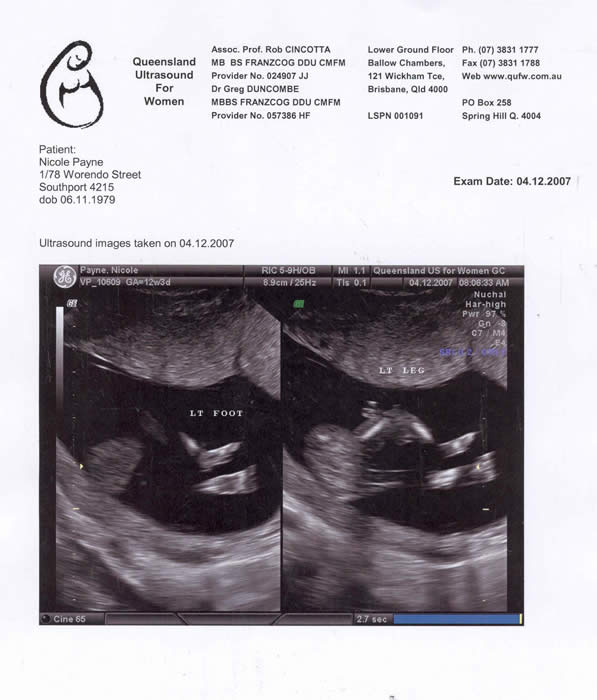

Our Baby at 13 weeks